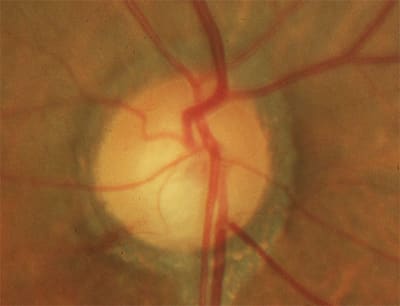

Shallow optic nerve cups and inferior neuroretinal rim thinning in each eye are indicative of normal-tension glaucoma in a 65-year-old woman, and the right optic nerve showed a disc hemorrhage inferotemporally before treatment was initiated.